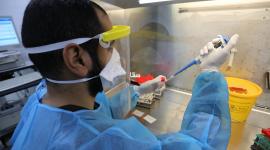

بالفيديو جديد أوميكرون المتحور الجديد

3 وفيات وتسجيل 99 إصابة بكورونا في غزة

الصحة: 3 وفيات و358 إصابة جديدة بكورونا بالضفة وغزة

وفاة و130 إصابة جديدة بكورونا في غزة

الكشف عن مدى نجاعة التطعيم ضد طفرة أوميكون الجديدة

الصحة: 4 وفيات و360 إصابة جديدة بكورونا بالضفة وغزة

الصحة العالمية: خطر "أوميكرون" مرتفع للغاية

138 إصابة جديدة بفيروس كورونا في غزة

الصحة الإسرائيلية: التطعيم يقاوم الطفرة الجديدة "اوميكرون"

تسجيل 70 إصابة جديدة بكورونا في غزة

رام الله: اجتماع طارئ الأحد لبحث الحالة الوبائية

الصحة: 3 وفيات و125 إصابة جديدة بكورونا بالضفة وغزة